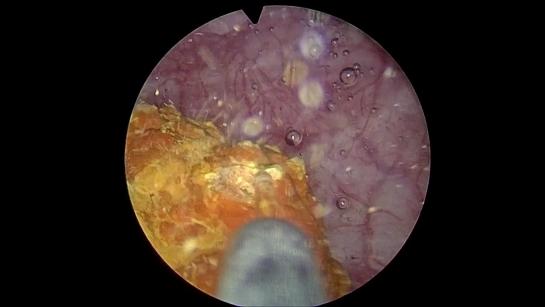

ТУР, тулиевая и гольмиевая энуклеация аденомы простаты 2,457 views 11 months ago 2 minutes, 44 seconds Uploaded by Медицинский центр «МИРТ» г. Кострома Related videos 1:53 1:13 1:15 1:51 5:29 2:20 1:25 3:12 2:43 4:14 1:55 1:34 1:11 2:18 4:32 2:54 6:35 5:57 1:45 1:15 1:18 10:00 1:13 2:02 6:05 4:05 7:49 4:30 62:00 0:40 1:16 5:08 0:55 2:20 2:40 1:31